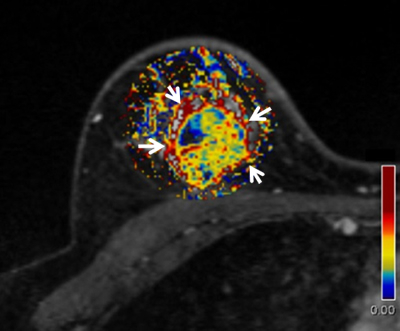

DCE-MR images of triple-negative breast cancer.

The image shows a parametric color map of ve, which is a quantitative parameter referring to volume of stromal space. Peripheral tumor area shows higher ve values (red area, arrows). Intra-tumoral area includes regions with lower ve values (blue area).